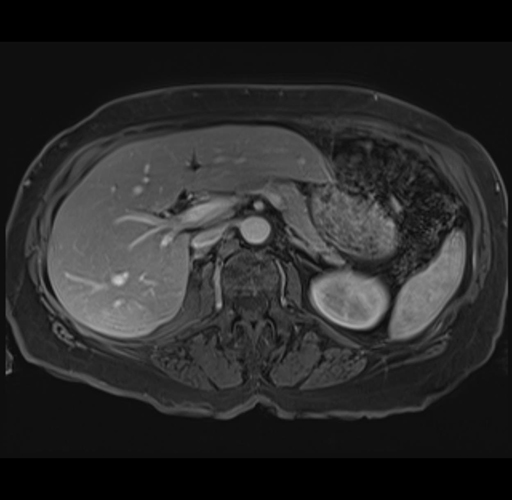

MRI T1